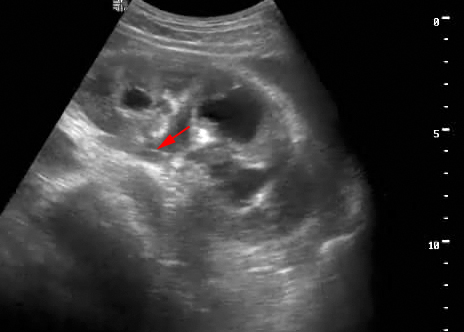

Пациент с подтвержденным туберкулезом почки

Видим длительно существующий гидронефроз вследствие процесса в области лоханочно-мочеточникового сегмента (видео 1), с утолщением стенок ЧЛС и истончением паренхимы почки - наиболее частая причина у взрослых - туберкулез.